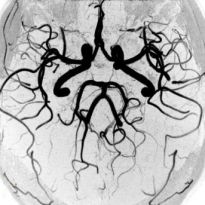

Ангиография

Одним из самых популярных методов обследования сосудистой системы считается ангиография. Эта методика предполагает введение в кровь пациента специального контрастирующего вещества. После того как оно равномерно распределится по всем артериям, делается рентгеновский снимок. На нем хороши видны все патологии.

Такое обследование может проводиться при помощи обычного рентгенографа или под контролем компьютерной томографии. Контрастирующее вещество полностью безвредно для человека. Спустя определенное время оно полностью выводится из организма естественным путем.